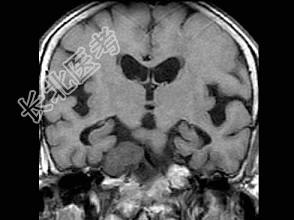

- 单项选择题男,46岁, 面部肌肉麻木、疼痛,咀嚼困难, 牙痛,MRI检查如图, 最可能的诊断是 ( )

B、三叉神经鞘瘤